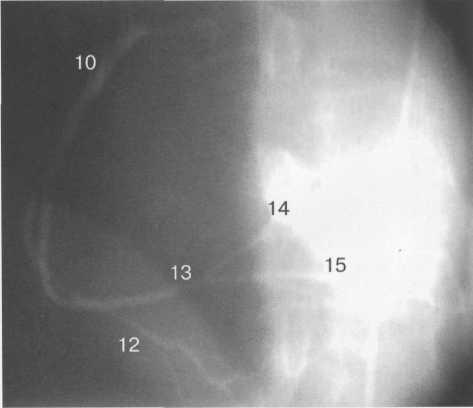

Анатомия коронарных артерий: КТ-изображения